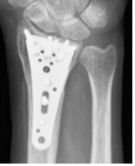

橈骨遠位端骨折に対する鏡視併用手術

橈骨遠位端骨折は頻度の高い骨折の一つで、特に関節内骨折については関節鏡を併用し従来のX線のみでは整復が不十分な関節面の整復を行っています。

骨折治療に加えて骨折の予防に骨粗しょう症の治療の導入も積極的に行っています。